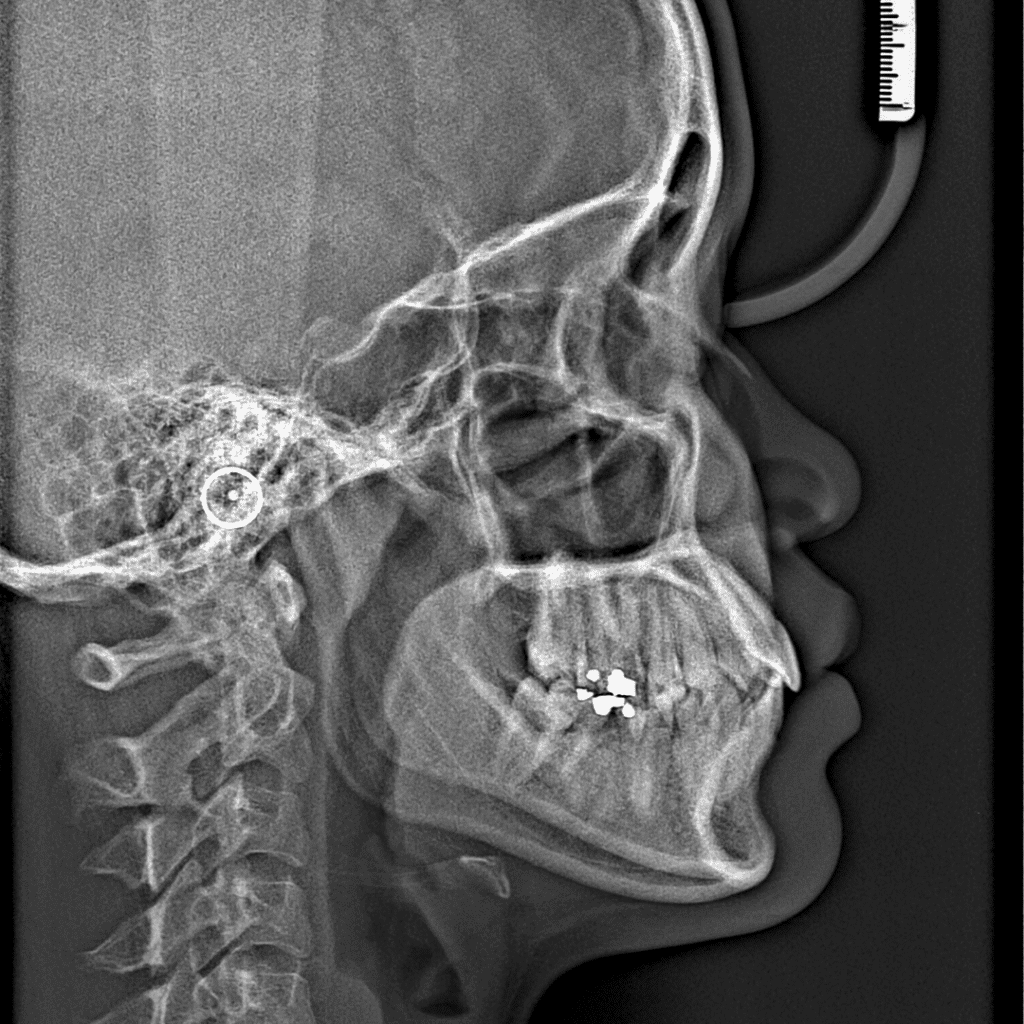

Temporomandibular Joint Surgery

drosmanakinciTemporomandibular Joint (TMJ) Surgery in Turkey: Cost, Benefits and Patient Guide Temporomandibular joint (TMJ) disorders…

Challenges in the Diagnosis and Treatment of Temporomandibular Joint (TMJ) Disorders

drosmanakinciChallenges in the Diagnosis and Treatment of Temporomandibular Joint (TMJ) Disorders Temporomandibular joint (TMJ) disorders…